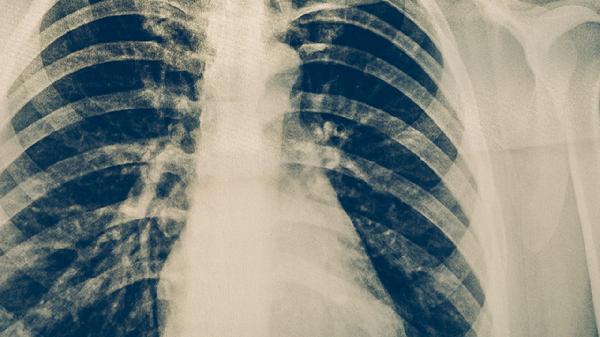

周围型肺癌患者可遵医嘱使用吉非替尼片、盐酸厄洛替尼片、贝伐珠单抗注射液、注射用培美曲塞二钠、卡铂注射液等药物。周围型肺癌的治疗需根据病理类型、基因检测结果及患者身体状况制定个体化方案,药物选择涉及靶向治疗、化疗、抗血管生成治疗等多种方式。